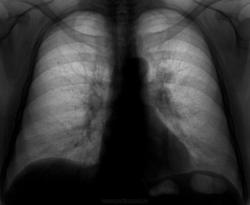

Отправил женщину на консультацию в ОНКО, а там (по их заключению) всего навсего хр.бронхит. Думаю, сколько прокленов было в мою сторону...

А как же образование в области головки левого корня? В онко как дообследовали? А книзу и медиальнее от образования вроде как лимфоузел...

Разделяю мнение коллеги- это не норма, нельзя ли представить снимок легких в левой боковой проекции?

Саркоидоз?

Я бы в первую очередь исключал метастатический процесс; во вторую, согласен в Викторм Владимировичем, саркоидоз.

Поднять флюороархив и смотреть динамику. Для метастазов, ИМХО, не очень ровный контур. Саркоидоз? А изменения в правом легком?

Некрасиво плохо говорить о коллегах,но такую тень нельзя не заметить.Особенно в специализированном учреждении.

Сам тоже лентяйУлыбаюсь, но для онкологов делаю прямой и боковой. Заключение онкологов - откровенный ляп, скорее всего будет центральный рак левого легкого.